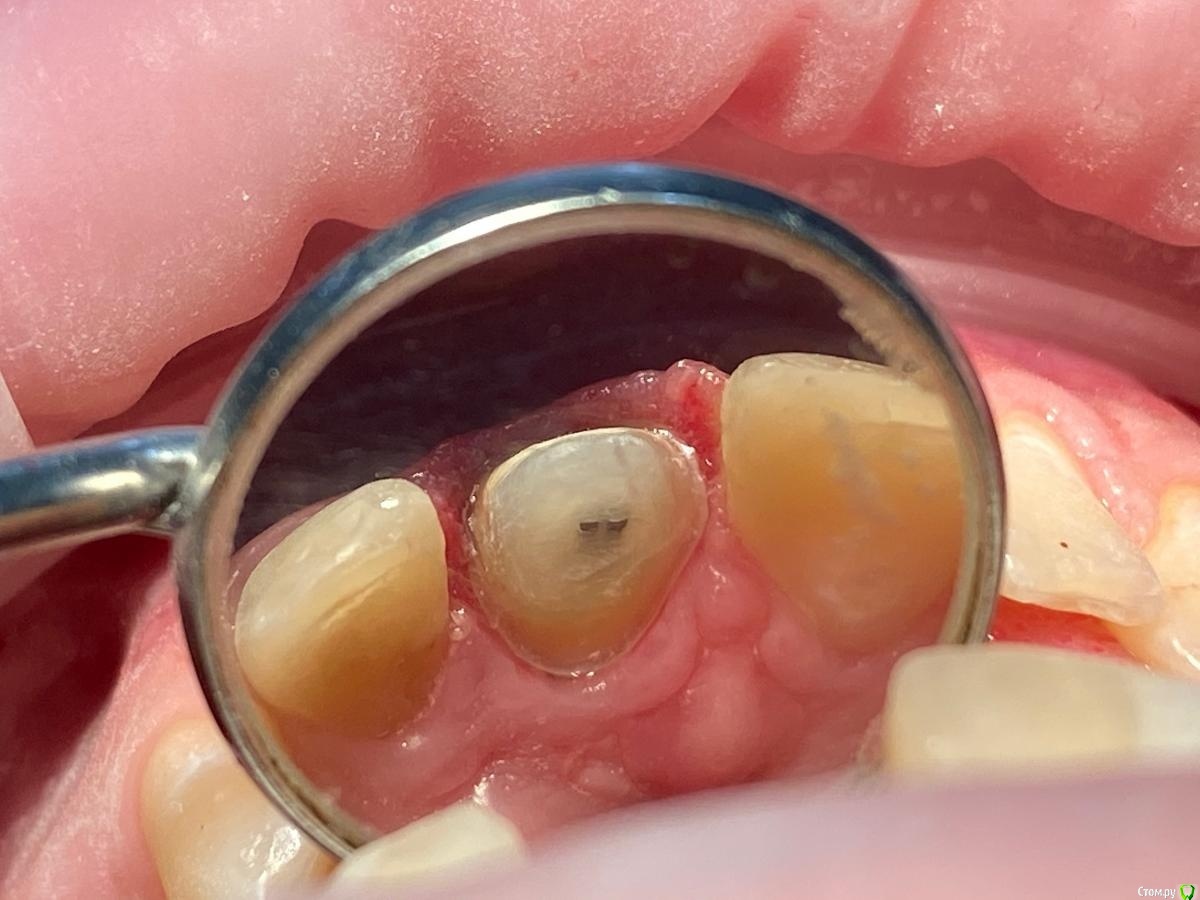

Женька Опубликовано 20 января, 2021 Автор Поделиться Опубликовано 20 января, 2021 Спасибо, коллеги. Я вас понял. Расскажите пожалуйста, как вы учились препарировать с уступом? Сегодня препарировал 2.1... 2 часа я мучал пациента (еще и г**но-времяшку делал). В итого получилось не очень как по мне... Посмотрите фото... это же просто стыд. Конусность запилена, уступ весь кривой-косой. Пересмотрел кучку видео по препу. Веб Артёма Олексика по полной коронке. Как научиться? Ссылка на комментарий

chervoncevdaniil Опубликовано 20 января, 2021 Поделиться Опубликовано 20 января, 2021 Стыда никакого нет,конусность,конечно,избыточна,вы сами видите.но с учетом того,что культя зуба не маленькая по размером,в данном случае при точной коронке проблем не будет.Все нормально,продолжайте работать,с каждым зубов будет получаться быстрее и аккуратнее 2 Ссылка на комментарий